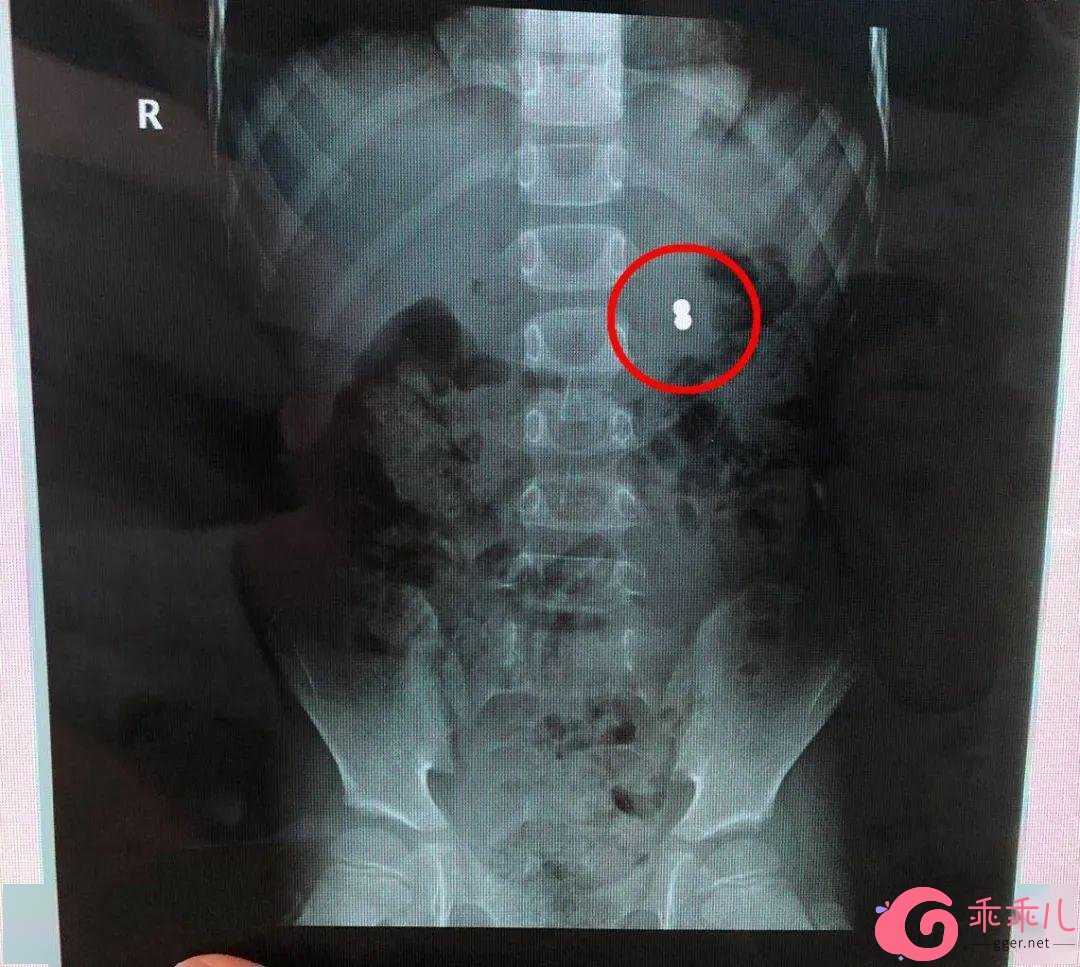

父母带着豪豪再次到医院检查,腹部立位片见左上腹异物,胃镜下发现只有一枚磁珠嵌顿于胃体大弯皱褶处,另一枚相邻的磁珠可能已经穿透胃壁进入腹腔,加之周围粘膜充血、糜烂、水肿。

B超提示:两颗直径均为5mm的磁力珠相邻排列,一颗磁珠在胃壁粘膜层肌层嵌顿,另一颗磁珠已穿破了浆膜层,且浆膜层已粘连包裹显示不清,周围大网膜水肿、粘连。

通过手术抓取, 两颗磁力珠被顺利取出。